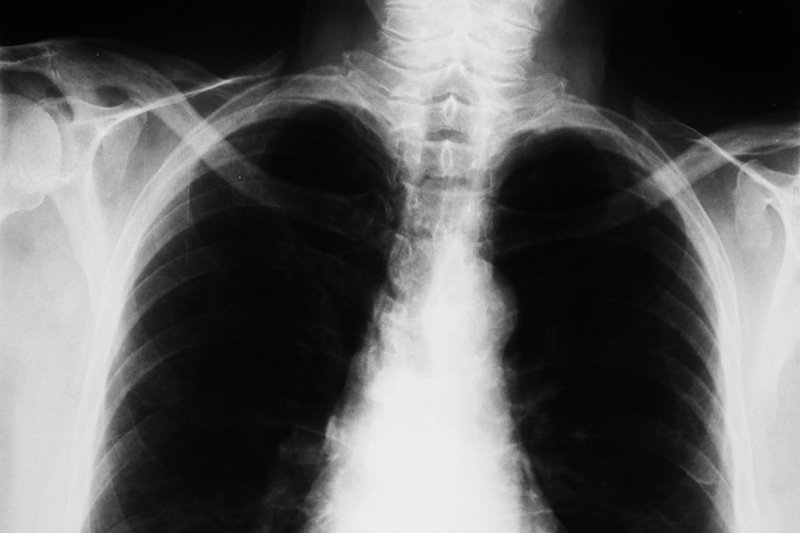

U pracownika jednej z wrocławskich szkół zdiagnozowano gruźlicę. Rodzice uczniów są zaniepokojeni, a lekarze szykują się do przebadania ponad ośmiuset osób na obecność prątków tej choroby. Czy przypadłość, która większości osób kojarzy się z zamierzchłymi czasami, wciąż stanowi realne zagrożenie?

We wrocławskiej podstawówce na gruźlicę zachorował konserwator szkolny, donosi "Gazeta Wrocławska".Wszyscy uczniowie oraz personel będą teraz musieli zostać przebadani. Czy gruźlica, na którą zmarł Fryderyk Chopin, i której Tomasza Manna poświęcił wiele miejsca w "Czarodziejskiej Górze", na początku XXI wieku wciąż jest groźna? Zapytałem o to doktora Jacka Jagodzińskiego z Mazowieckiego Centrum Leczenia Chorób Płuc i Gruźlicy w Otwocku.

W pewnym momencie rząd PRL podjął decyzję o szeroko zakrojonej akcji walki z chorobą. Powstały specjalistyczne placówki, w rządzie wydzielono specjalny “pion” do walki z chorobą, rozbudowano sieć sanatoriów i wprowadzono leki przeciwgruźlicze. Wiele antybiotyków przydatnych także w innych schorzeniach rezerwowano specjalnie dla gruźlików. W 1959 roku sprawę zwalczania choroby uregulowano nawet w specjalnej ustawie. Nie bez znaczenia było też oczywiście ogólne podniesienie poziomu życia społeczeństwa oraz takie inicjatywy, jak np. objazdowa stacja RTG jeżdżąca po polskich wsiach.